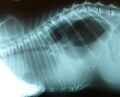

| current | 20:38, 25 June 2008 | 500 × 406 (37 KB) | Christina (talk | contribs) |